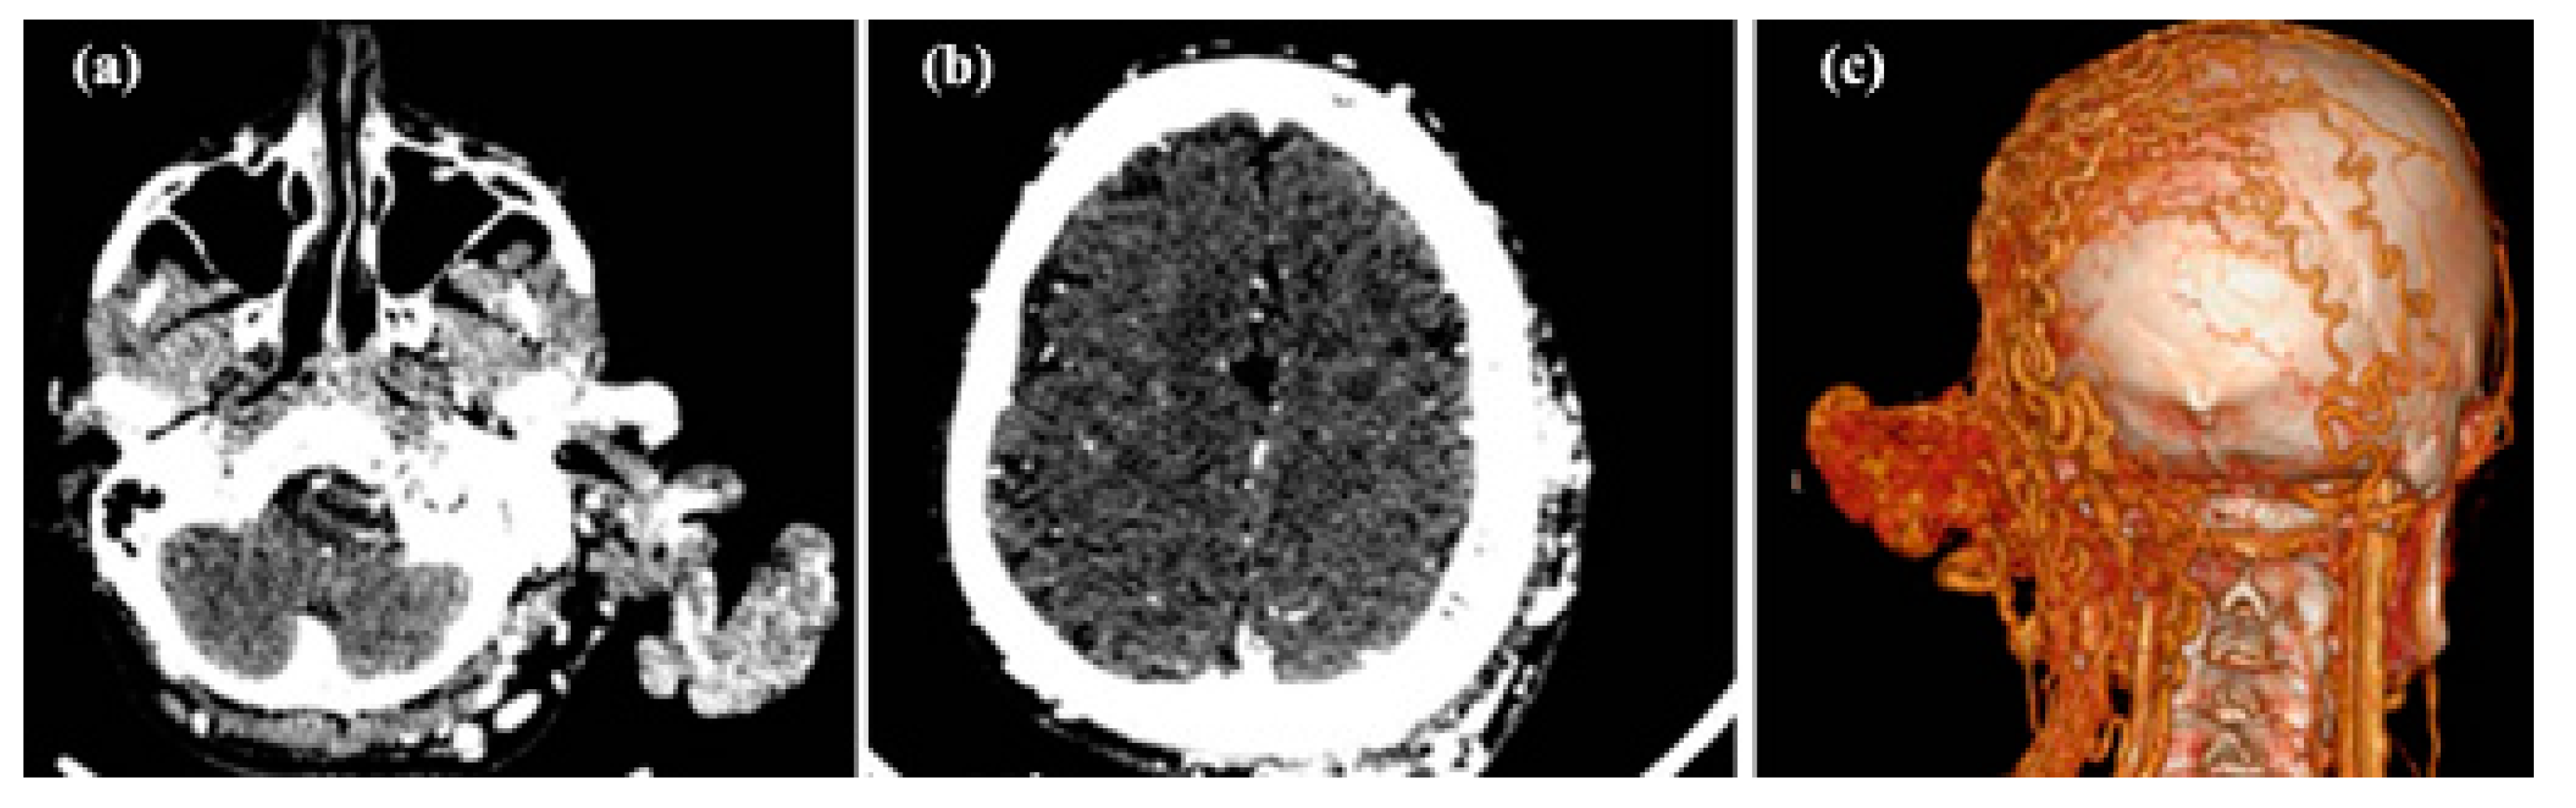

3.3. Arteriovenous Malformations

3.3.1. Clinical Data

3.3.2. Diagnosis

3.3.3. Therapy